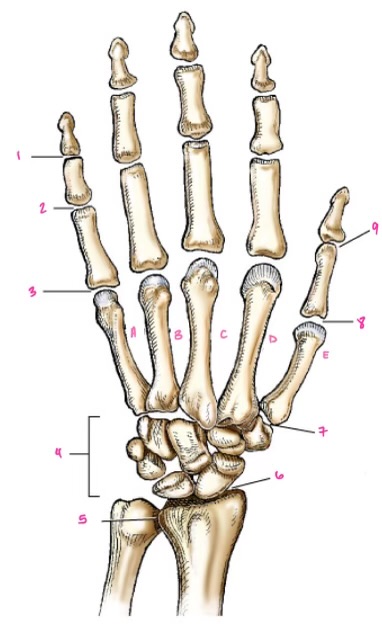

1

1

Hamate

2

2

Capitate

3

3

pisiform

4

9

Trapezoid

5

10

Trapezium

6

11

Scaphoid

7

14

Lunate

8

15

Triquetrum

9

16

Pisiform

10

17

Capitate

11

18

Hamate

1

Distal interphalangeal

13

2

Proximal Interphalangeal

14

3

Metacarpophalangeal

15

4

Intercapals

16

5

Distal radioulnar

17

6

Radiocarpal

18

7

Carpometacarpals

19

8

Metacarpophalangeal

20

9

Interphalangeal

7

Trapezoid

22

8

Trapzium

23

9

Capitate

24

10

Scaphoid

25

11

Lunate

26

13

Carpus

27

14

Triquetrul

28

15

Hamate

29

16

Metacarpus

30

17

Phalanxes